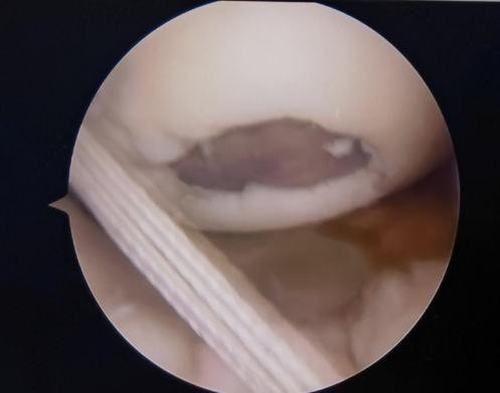

關節(jié)鏡下軟骨損傷

經(jīng)患者同意后,李鵬主任手術團隊制定詳細手術方案。手術如期進行,經(jīng)團隊密切配合,對幾位患者分別順利完成關節(jié)鏡下膝關節(jié)鏡鏡檢、關節(jié)清理、股薄肌半腱肌取腱移植術、前交叉韌帶重建術、軟骨損傷微骨折術、半月板縫合修整術等。

鏡下重建前交叉韌帶走形、張力良好